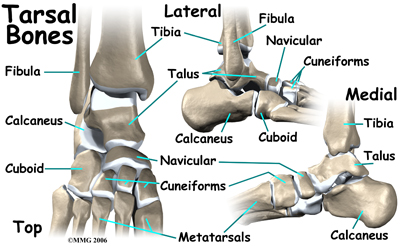

The lower leg is made up of two main bones. The larger bone is the shin bone, called the tibia. The smaller bone runs along the outside of the tibia it's called the fibula. These bones, along with a saddle shaped bone at the top of the foot called the talus form the ankle.

The foot has many bones. There are seven short bones below the ankle called the . The big square bone on the outside of the middle of the foot is called the cuboid. The long bones of the foot from the arch to the joints of the toes are called the metatarsals.

Bunk-bed fractures are caused by jumping. The cuboid bone and first metatarsal in the foot are the bones that are usually broken in this type of injury.